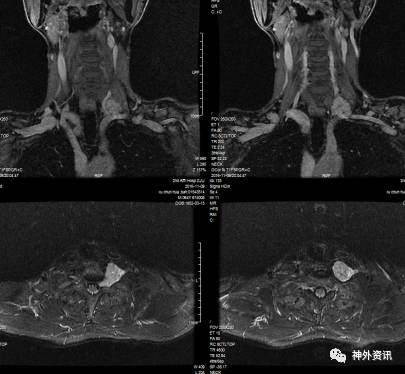

入院后进一步行增强MRI检查,显示胸1左侧椎旁间隙可见大小约为24.9x34.2x37.8mm(左右x前后x上下)等T1长T2异常信号影,增强后不均匀轻度强化,其内未见脂肪信号,部分向内进入颈7-胸1椎间孔,椎间孔扩大。周边与颈总动脉、锁骨下动脉关系密切。肿瘤大体位于胸骨切迹以上,最低水平位于左侧胸膜顶,向胸腔突入(图1)。影像诊断:颈胸交界区左侧椎旁间隙肿块,考虑臂丛神经鞘瘤。

图1. 术前MRI可见肿瘤位于颈7-胸1水平,不均匀轻度强化。部分向内进入颈7胸1椎间孔,椎间孔扩大。肿瘤大体位于胸骨切迹以上,最低水平位于左侧胸膜顶,向胸腔突入。